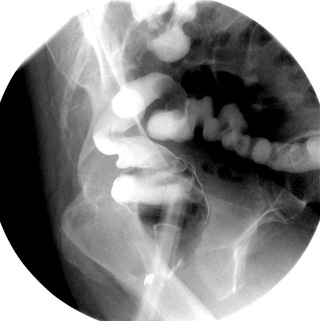

- When the sigmoid colon is well filled, take a

spot image of the rectosigmoid colon in the LPO position.

NOTE: Rectosigmoid spot films are

obtained early because reflux of barium into the cecum and terminal

ileum may later obscure this area.